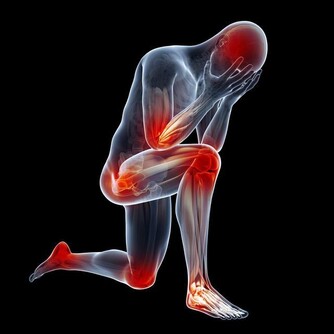

當然,除了以上的原因會導致人體的汗液分泌增多,還有一些病理性的原因也是導致人體的汗液增多的,比如腎虛、脾虛、氣虛、甲亢、糖尿病、低血糖等等疾病,所以說當發現人體出汗量比較大時,不一定就是腎虛,是不能一概而論的。

不少異常的“靜汗”需要引起注意,比如自汗、盜汗等。有些人不熱、不運動時前心後背會出汗,且容易疲勞、感冒、心慌,特別怕風怕冷,這叫自汗,是氣虛的表現。夜晚一睡著就出汗,叫盜汗,是陰虛的表現。

無論冬夏,在白天不活動或輕微活動的情況下,常汗出不止。常有身體虛弱、說話語聲較低、食慾差、易感冒等特點,中醫認為是氣虛的表現。

睡著出汗,醒來汗止,中醫稱為“盜汗”。常有手腳心熱、心煩、面部發紅發熱、口咽乾燥等特點,中醫認為是陰虛表現。